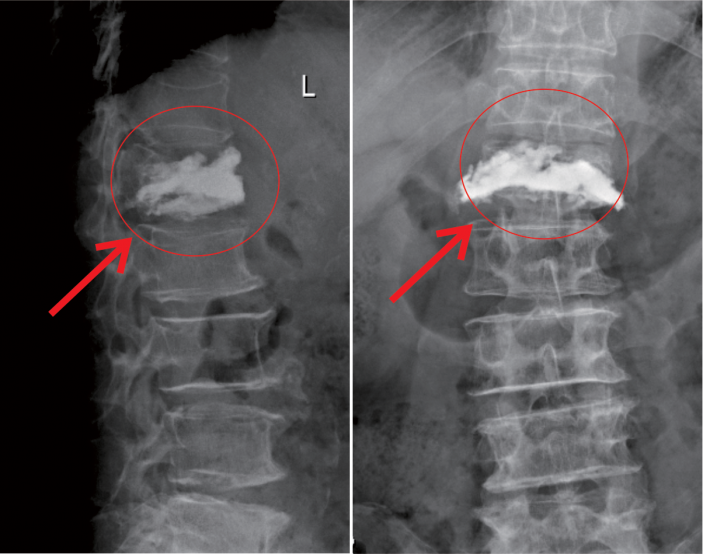

在我院先進的術中三維CT引導下,杜教授确定L1雙側椎弓根進針點,娴熟地将穿刺針穿入L1椎體,經穿刺針建立通道将約11ml骨水泥注入坍塌的椎體中。術中監視,注入的骨水泥逐漸支撐起原本壓縮空洞的椎體。骨水泥凝固後,病變的椎體迅速恢複了承重能力。手術持續約40分鍾,開展非常成功,術後老人的疼痛馬上消失,翻身也無疼痛,第二天就能使用助步器下地行走。

△術中注入骨水泥約11ml